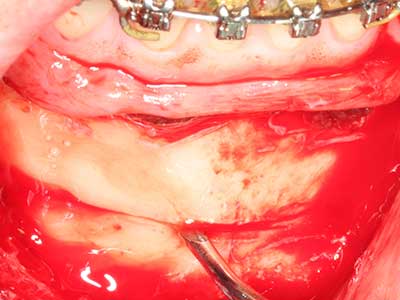

Bone tissue is not simply a mineral structure but also contains a substantial proportion of collagen fibres. This means it not only has good compressive strength but also a degree of flexibility, which can be taken advantage of when performing bone augmentations. In the classical expansion procedure using bone splitting, the atrophied alveolar ridge is split longitudinally and carefully expanded after reaching an adequate osteotomy depth (Fig. 13-16), ideally without substantial removal of the periosteum (Brugnami, Caiazzo et al. 2014, Stricker, Fleiner et al. 2014). Screw and plate systems with increasing expansion distance have proven effective in separating the two bone lamellae while remaining below the fracture threshold. In general, residual bone widths of at least 3–4 mm are required (Chiapasco, Zaniboni et al. 2006) to guarantee adequate flexibility and sufficient bone coverage of the future implants. If necessary, a vertical relief osteotomy on one or both sides can improve flexibility. A combination with additional augmentation techniques, particularly on the buccal side, has been described as an alternative to the classical technique.

The splitting procedure is particularly atraumatic and there is no significant loss of dimension when using piezosaws, and there are no significant differences between implants in split jaws and implants in an alveolar ridge without a bone deficit (Chiapasco, Zaniboni et al. 2006, Danza, Guidi et al. 2009). However, sufficient continuous irrigation is essential, particularly with locally restricted and deep splitting to prevent thermal stress in the apical osteotomy regions.